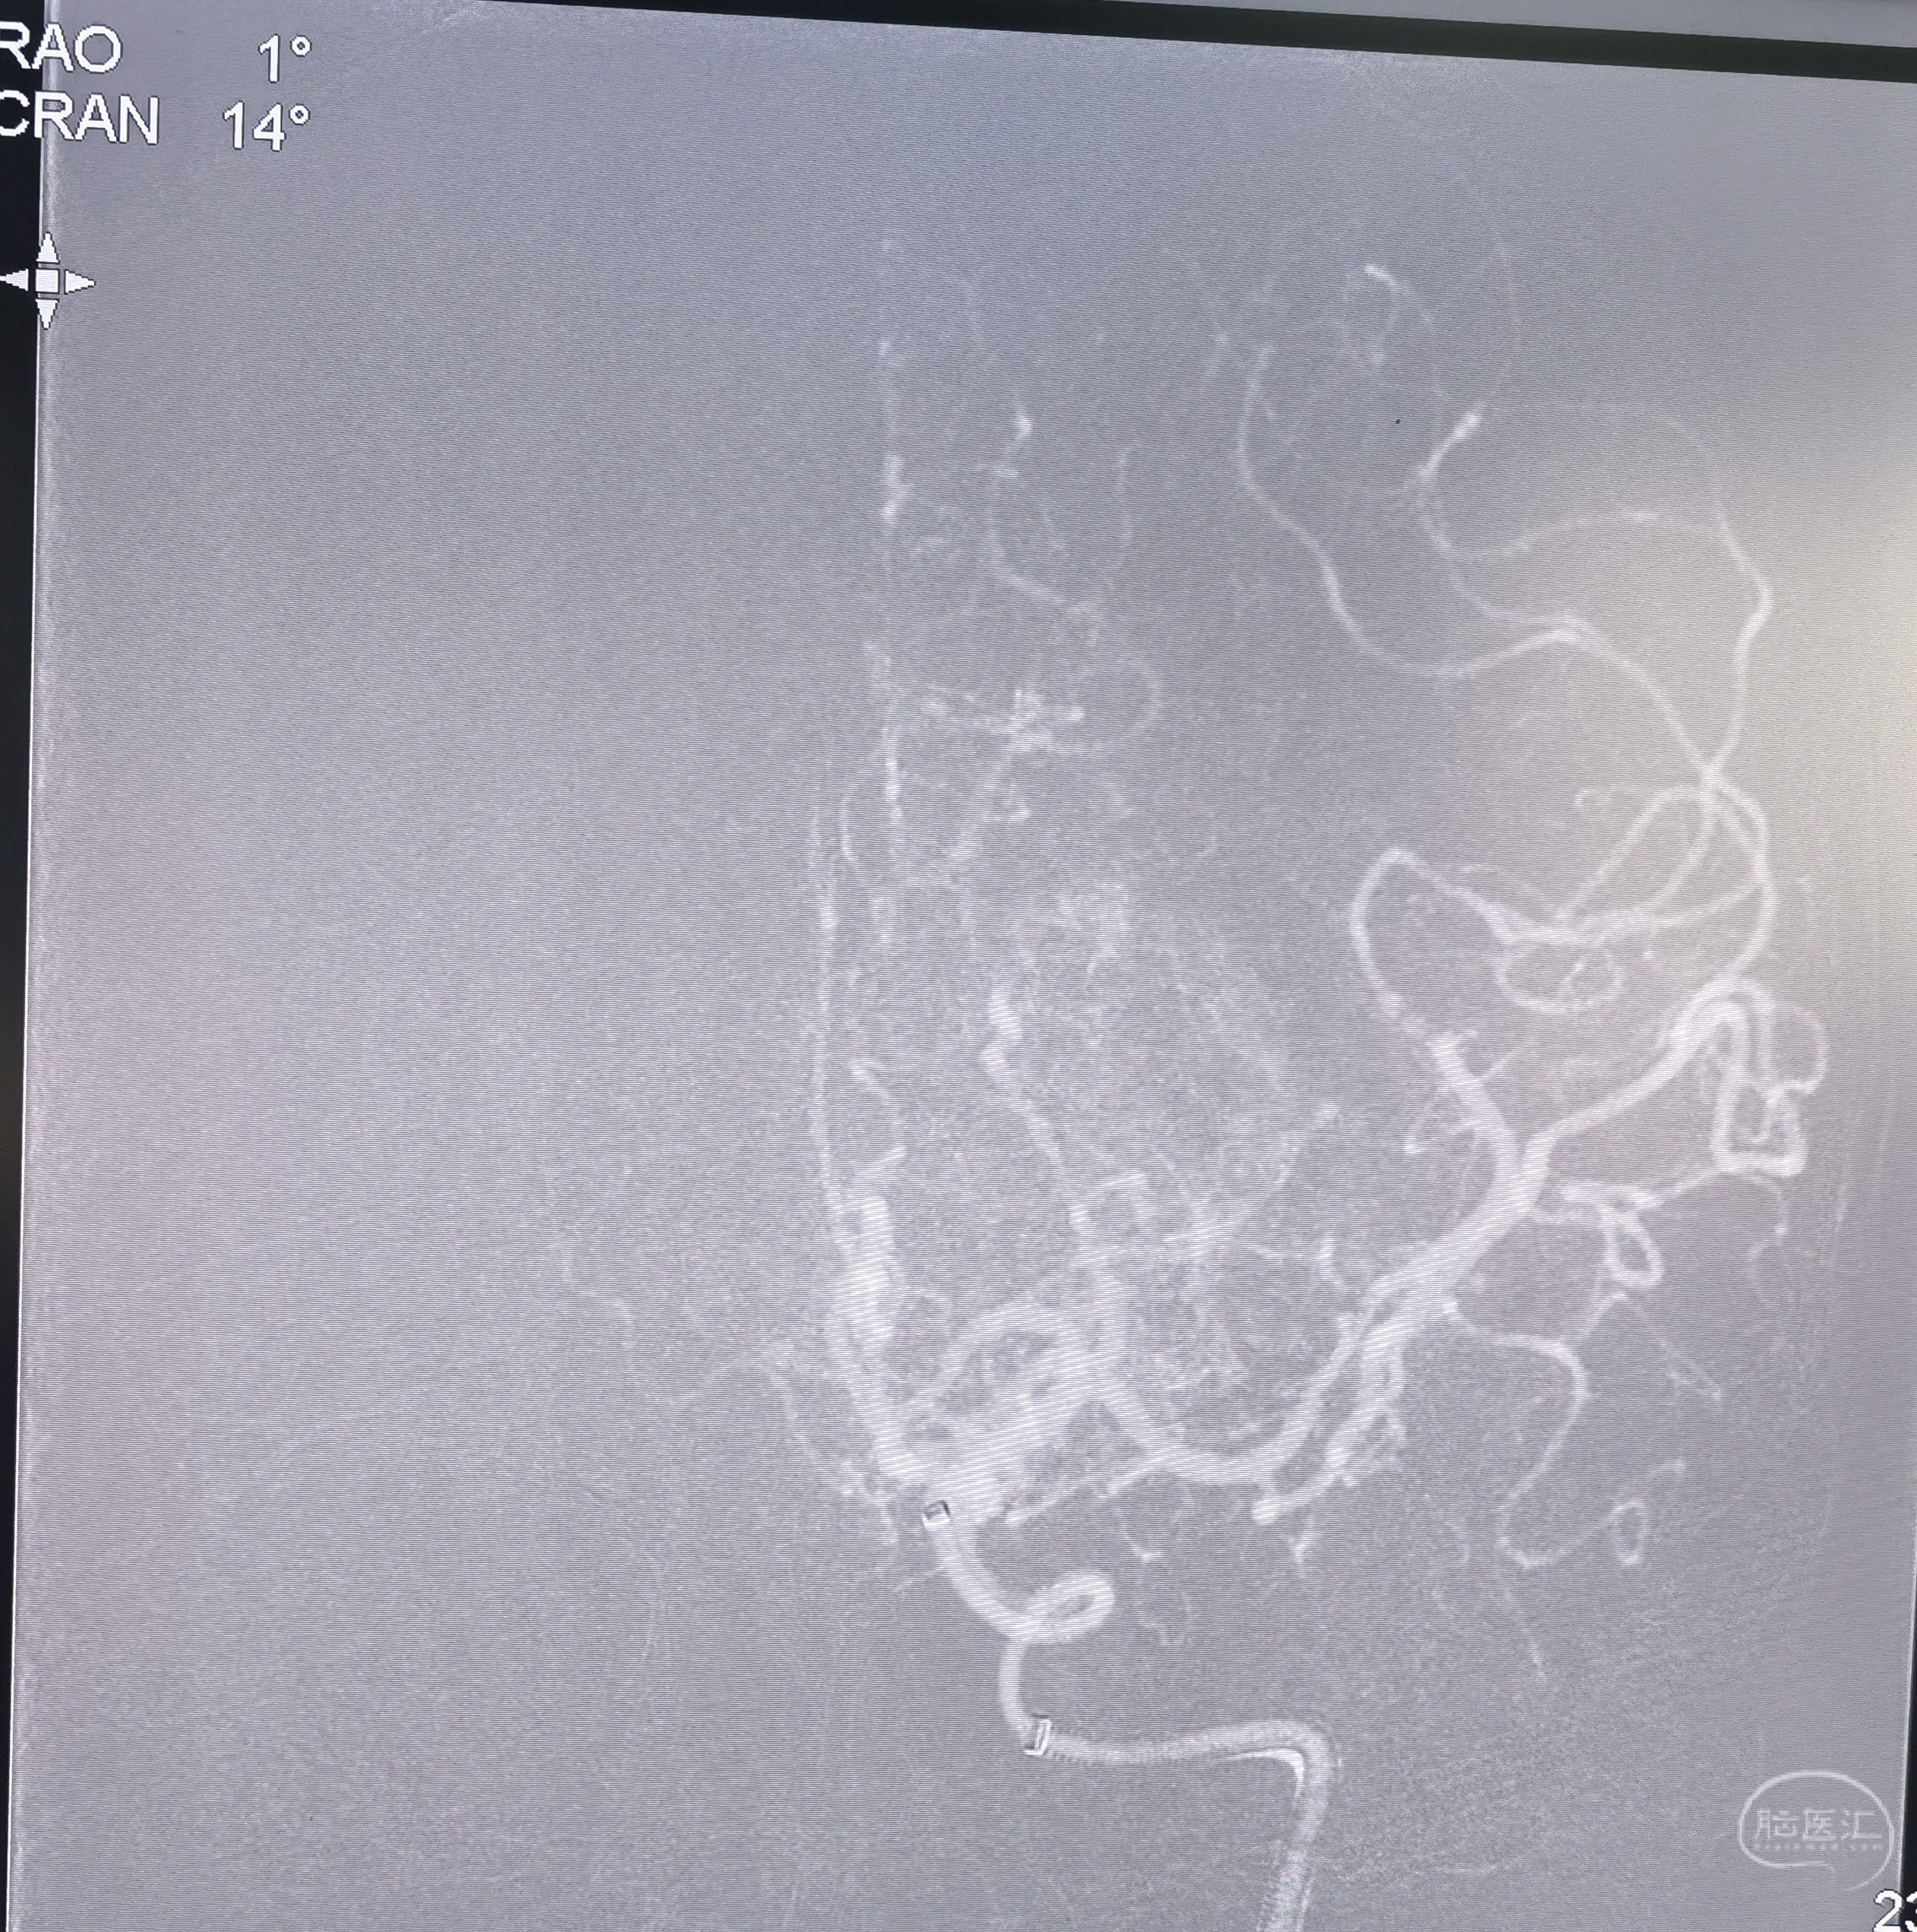

通过颈内动脉闭塞段后正位造影

通过颈内动脉闭塞段后侧位造影